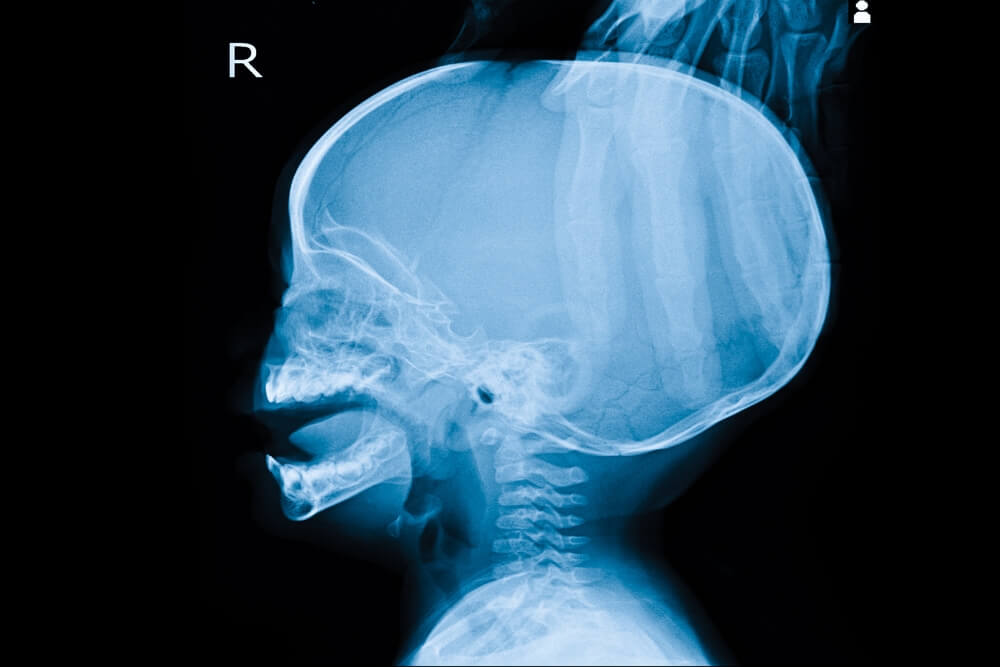

Hidrocefalia: síntomas y tratamiento

El organismo produce líquido cefalorraquídeo (LCR) continuamente. La hidrocefalia es un trastorno que se caracteriza por una acumulación anormal de líquido cefalorraquídeo (LCR) en el cerebro. Esa acumulación provoca un aumento excesivo de la presión en el cráneo.

En situaciones normales el LCR circula por el cerebro y la médula espinal a través de ventrículos, se almacena en depósitos conocidos como cisternas y pasa regularmente a la sangre. Si alguna circunstancia limita esa circulación, el líquido se acumula en ciertas regiones y ejerce una presión perjudicial sobre el tejido cerebral (hipertensión craneal). El exceso de presión intracraneal puede llegar a producir lesiones irreversibles.

- Pruebas de imagen, como una tomografía axial computarizada o una resonancia magnética, para detectar un aumento en el tamaño de los ventrículos.